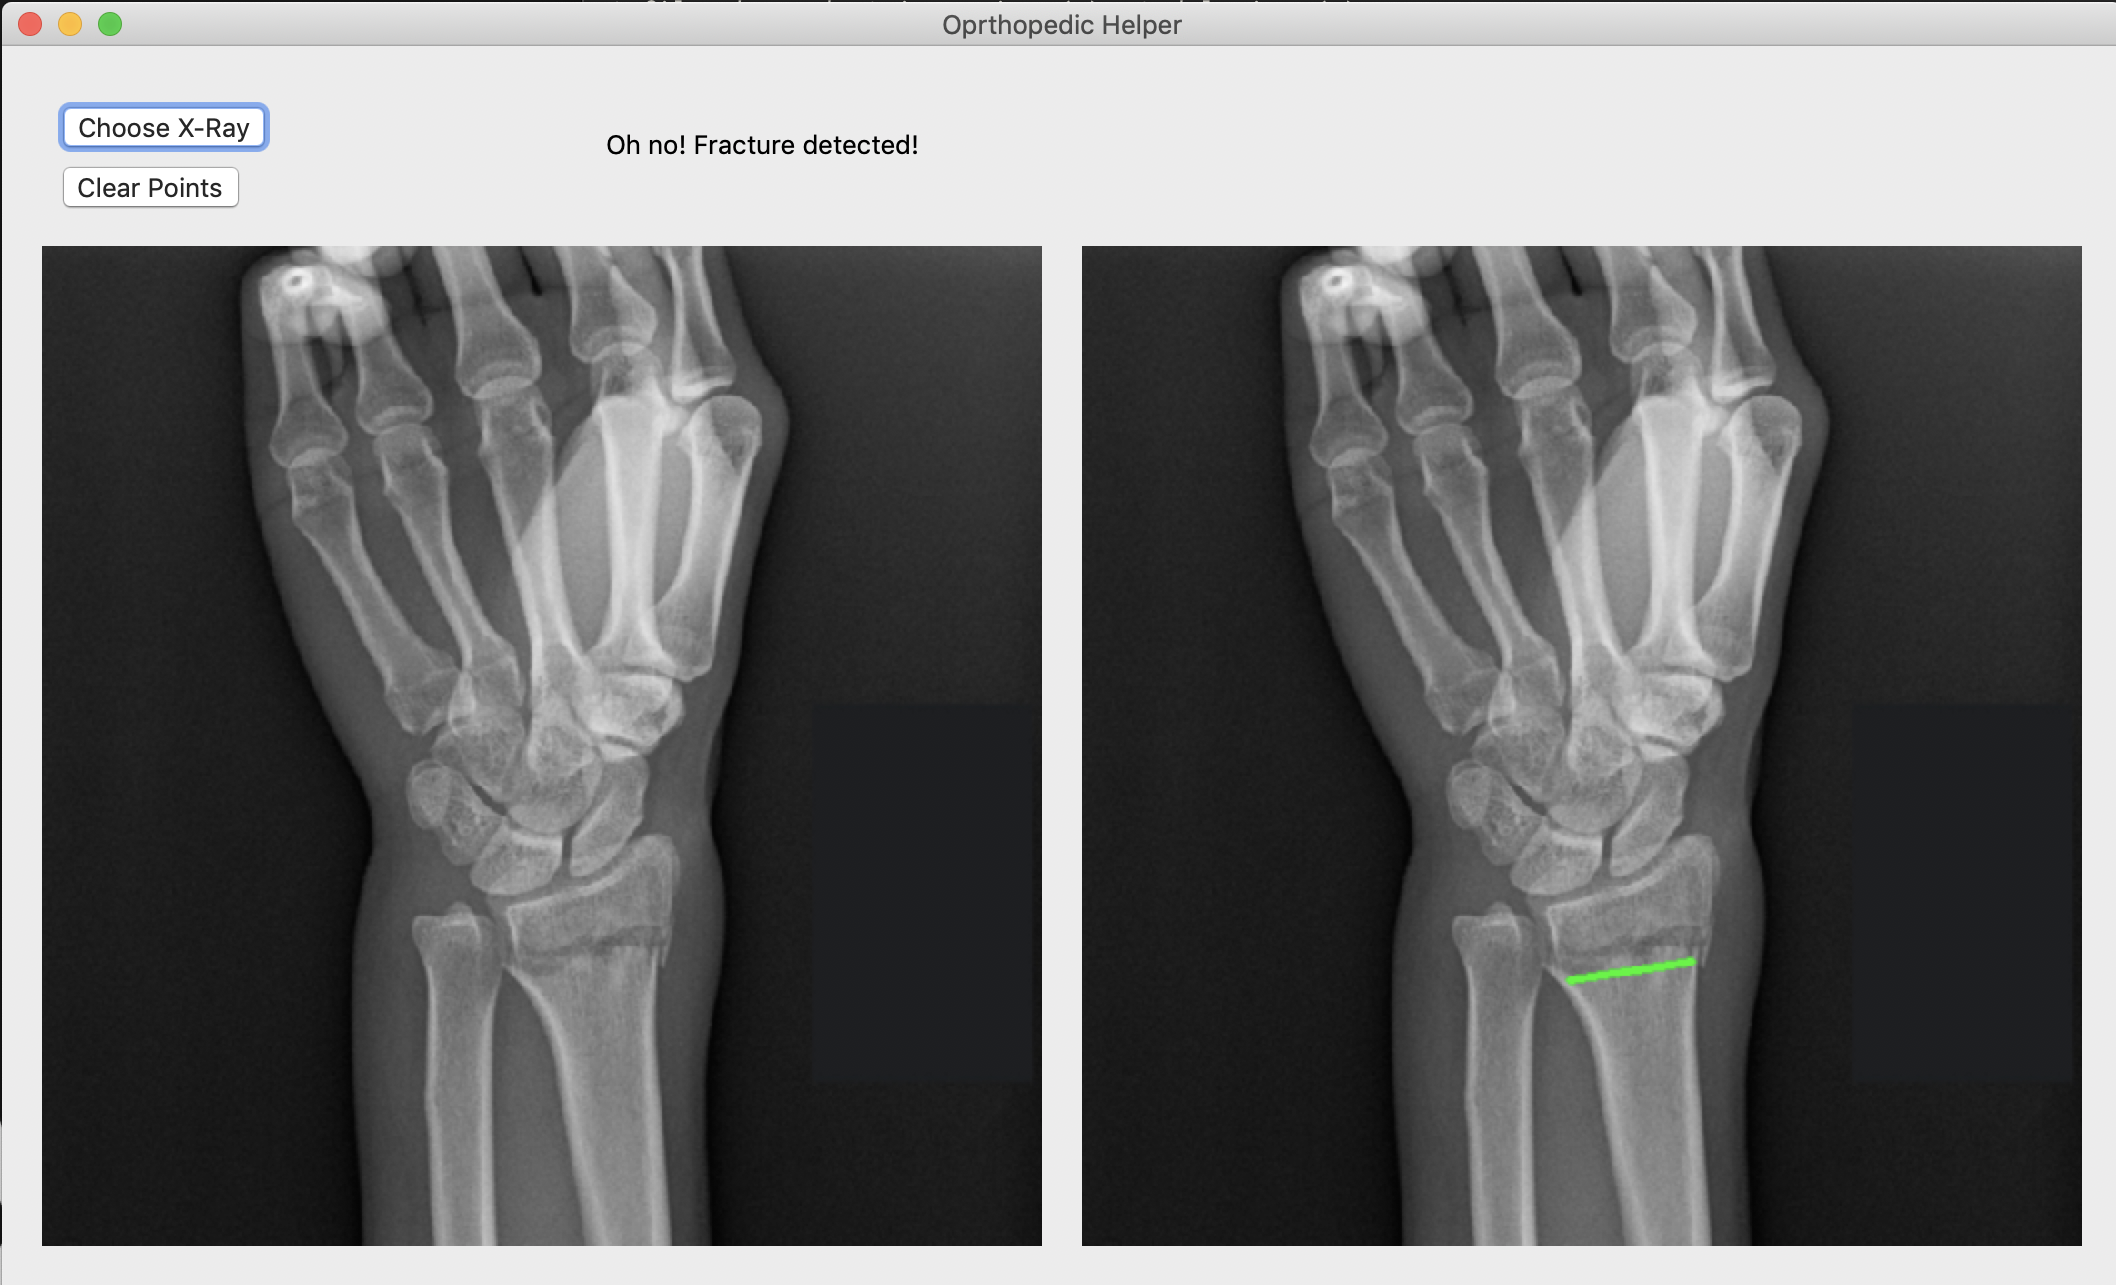

Broke Detector is a simple tool to help analyze the site of wrist injury. It helps doctors decide a) whether the bones are broken or not (which is admittedly very simple for humans, but not for computers) and b) provides tools such as a protractor to provide an objective measurement of how misaligned bones are. Broke Detector aims not to replace the orthopedist, but to aid them.

The actual detection algorithm is the guts of this project (no machine learning involved). The process is as follows: Thresholding: Reasons for this will be listed in the next section, we did this using color histograms to determine the percentile of certain pixel values. Edge detection: We used a simple Söbel kernel (however, not the default opencv one) to handle edge detection, as it was simple to detect only horizontal edges. Hough transform: This is the guts of the algorithm, which decides where horizontal lines are in the X-Ray. It sounds dumb, but choosing the lowest isolated horizontal line almost always results in finding the break in the bone. Flask: We developed a locally hosted web application which supports uploading from the computer. The HTML formatted site displays the results of the Python calculations.

While we were very passionate about doing something involving the X-rays, there were a couple issues with our process. The common state-of-the-art solutions to a problem like this would be stuffing a bunch of data into a faster R-CNN and let it handle the detection. However, we lacked both the volume and consistency of data to make this a reality: many of the research papers that tackled this problem partnered with a medical office, which would provide them a lot of consistent and annotated images to work with. Because of the hodgepodge of different variables that differ with each image we ripped off of Google images, we had to use techniques like color thresholding, as the brightness of what was bone and what was background differed from image to image. Even now, the algorithm isn't quite perfect. It still struggles to detect fractures that are close to the end of the radius/ulna.